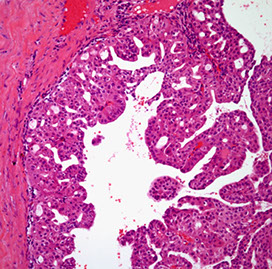

IPMN

Gross: mucous-producing tumors found in the larger ducts in the head of the pancreas and can be multifocal

- intraductal cystic dilatation c mucinous lining

Micro: distinguished from mucinous cystic neoplasm by lack of dense "ovarian"-type stroma and involvement of the ducts

IHC: (+) MUC2, CDX2, S100p

- MUC1

- has intestinal phenotype